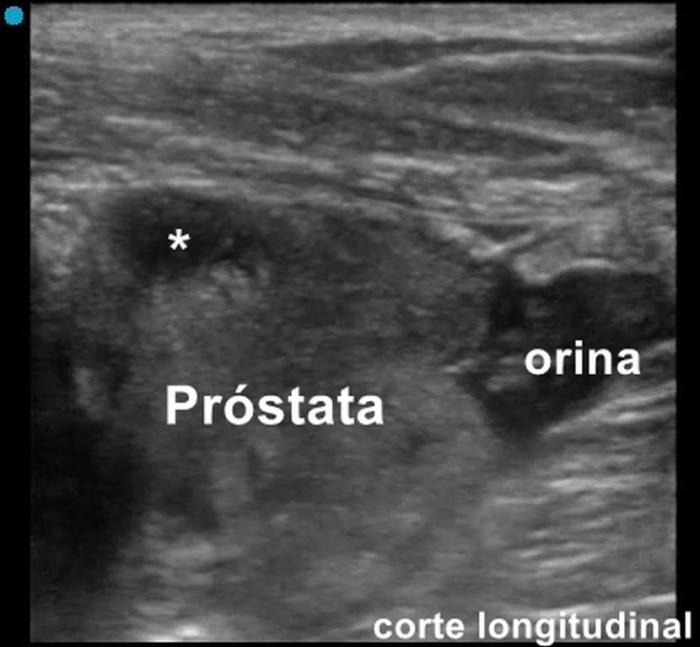

La ultrasonografía abdominal y de la cavidad pélvica permite identificar líquido libre, engrosamiento periuretral y cambios secundarios como hidronefrosis. En el caso de un paciente canino macho, muchas veces se detecta una prostatitis aguda y celulitis en el tejido subcutáneo de la región pélvica debido al contacto con la orina (Figura 1-3) (Vídeo 1). Sin embargo, rara vez demuestra de manera directa la fuga urinaria⁴.

Vídeo 1. Vídeo del paciente.